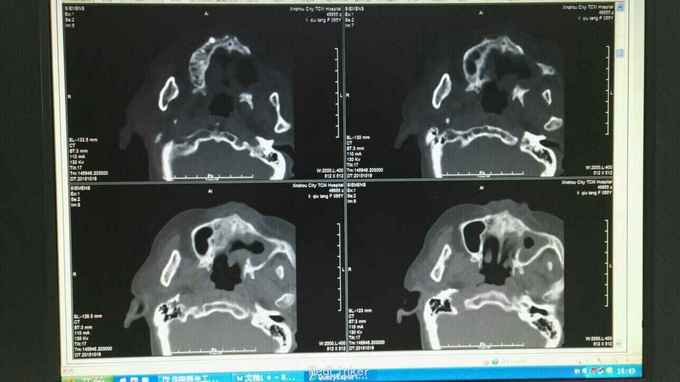

主诉:左上牙龈癌术后2月半余 病史:患者,女65岁,详见图:

查体、辅助检查见图:

诊断:左上牙龈癌术后复发 治疗:2015.10.21CT引导下行碘125粒子植入术,图为术前定位